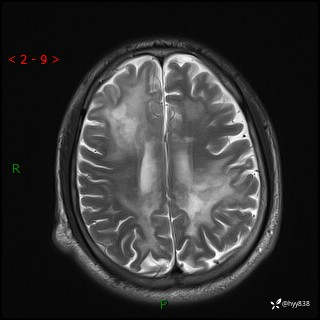

辅助检查:MRI

MRI T2WI